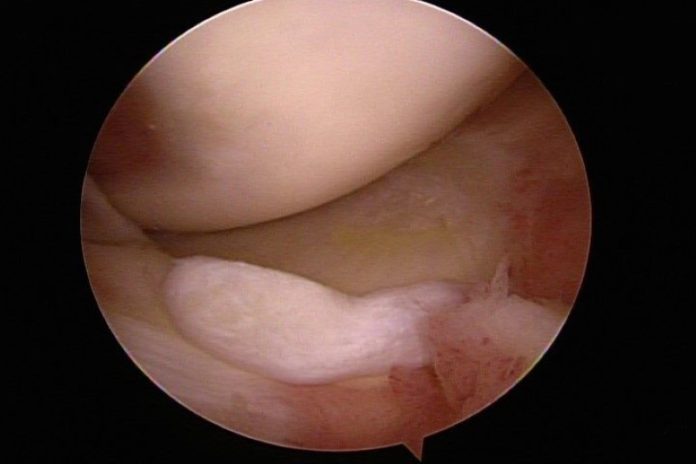

臺北市立聯合醫院忠孝院區骨科主治醫師林心畬表示,輕微的磨損注射玻尿酸潤滑即可緩解,但較嚴重的損傷會導致軟骨破裂,有時軟骨會移位,碎片會脫落,形成大問題。關節軟骨出現較大破損時,會有明顯的凹凸不平甚至會剝落形成碎片,活動時容易卡住,也會有突發的無力感,還會發炎腫脹產生關節內積水。休息跟吃消炎藥可暫時緩解,但症狀時常反覆,造成一大困擾,這時就會需要手術介入。

傳統手術需要切開整個關節來移除碎片或修補軟骨,傷口大,復原慢,有時還會遇到手術後沾黏僵硬的後遺症。但是現在內視鏡技術已經普及化,搭配關節專用的內視鏡器械,只需要三個小於一公分的傷口便可完成手術,手術後隔天傷口只會些微腫脹,通常一天內可以恢復獨立下床與走路,住院時間只需兩天一夜。

除了修補軟骨及移除碎片,手術中還可以詳細檢查關節內的狀況,若是發現不平整的皺壁或是發炎的滑膜組織也可同時清除,回復關節的順暢度,延長關節的使用年限。